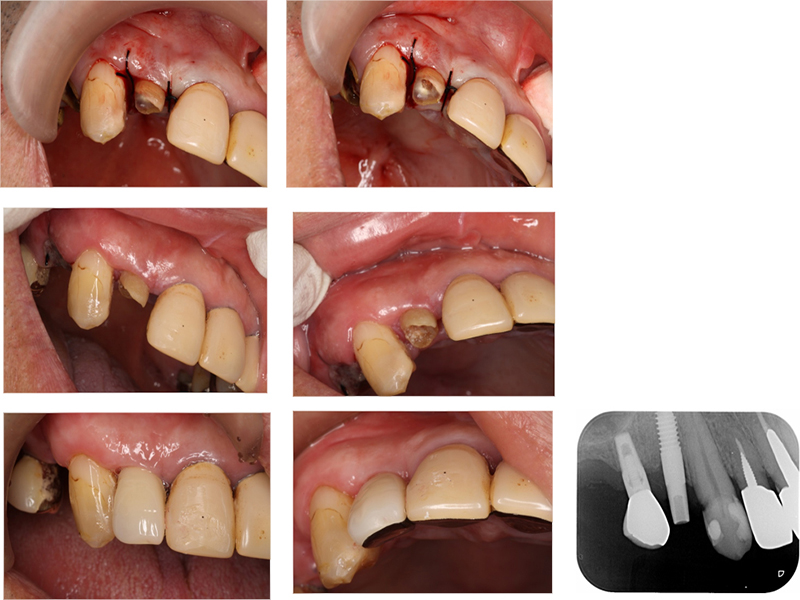

▼ ケース6.矯正的挺出

矯正開始前

矯正開始

矯正終了

補綴終了

矯正開始前、矯正終了時、補綴終了